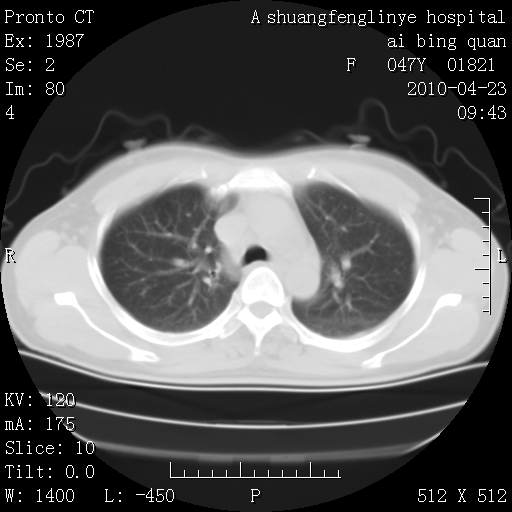

标题: CT25944:胸痛、气短、前几日高烧!肺Ca?请会诊! [打印本页]

标题: CT25944:胸痛、气短、前几日高烧!肺Ca?请会诊!

kaolv 周围型肺癌并同肺转移

双肺多发结节,考虑转移瘤,肺癌肺转移不除外

周围型肺癌并肺转移

双肺多发结节,部分密度较高,最大结节边缘光滑。临床有“胸痛、气短、前几日高烧”病史。首选考虑:右肺感染性病变!建议积极消炎后复查!

建议抗炎治疗后复查,排除肿瘤性病变。